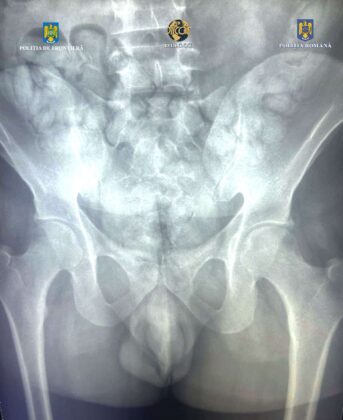

În urma controlului efectuat cu ajutorul unui scaner corporal cu raze X, în interiorul abdomenului inculpatului au fost observate mai multe formațiuni neobișnuite. Acestea nu corespundeau anatomiei umane. Bărbatul a fost condus la o unitate spitalicească. Pe parcursul internării, a eliminat un număr de 62 de cașete, ce conțineau aproximativ 350 de grame de substanță pulverulentă. Aceasta se află în curs de expertizare.